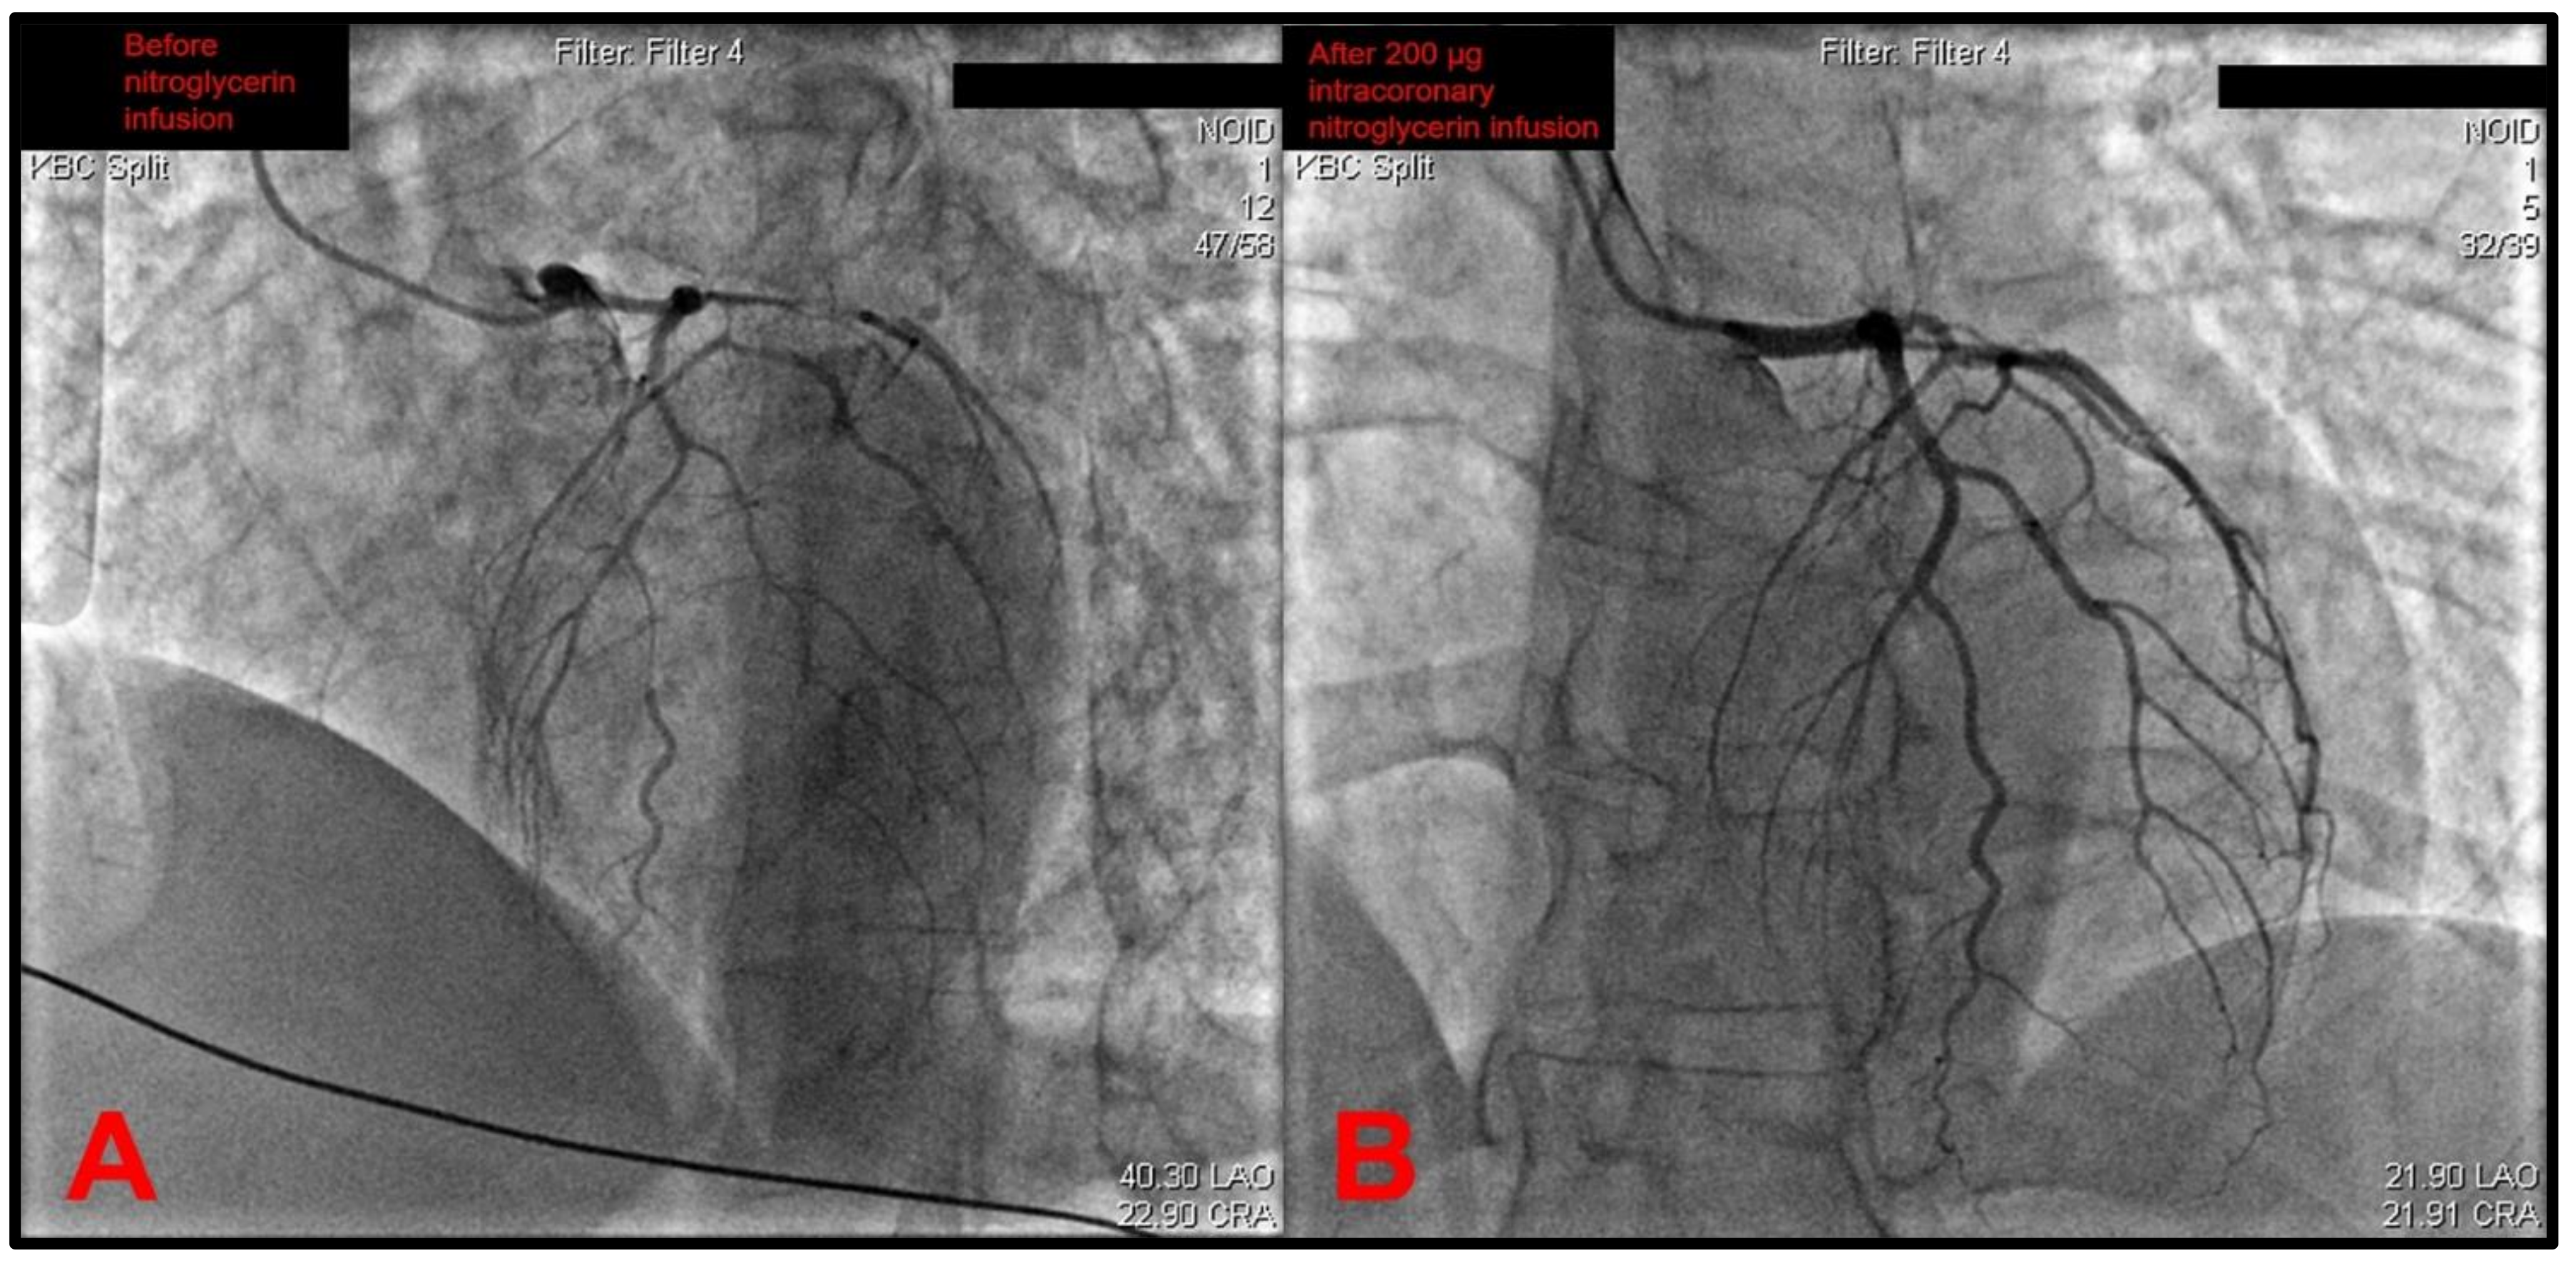

She was immediately transferred to cath lab from CCU, and an emergent coronary angiography was performed by intubating a right coronary artery (RCA), with the 6F diagnostic catheter showing a dominant high-caliber vessel giving off posterolateral (PL) and posterodescending (PD) branches with normal TIMI-3 flow and no signs of obstructive coronary disease (Figure 1).

The catheter was then exchanged, and the left coronary artery (LCA) was later intubated. This revealed a gracile left coronary circulation characterized by the narrow-caliber LM that was prone to spasm and a narrow caliber LAD that featured a slow flow as well as the angiographical picture of an intramural hematoma due to a spontaneous coronary artery dissection (SCAD) originating from the left main stem (Figure 2A). A differential diagnosis of severe diffuse coronary vasospasm was considered as well, given the narrow and gracile caliber of all vessels originating from the left main stem. The circumflex artery (Cx) was found to have a slow flow, and it also featured severe diffuse spasms. Furthermore, it also gave off a strong marginal branch that had slow flow and had a significantly larger diameter than the circumflex. The intermediate branch was also observed to be characterized by gracile morphology, slow flow, and subocclusion of the proximal segment. An intracoronary infusion of 200 μg of nitroglycerin significantly recovered the distal flow through the left coronary tree (Figure 2B). Although it would be an appropriate step to perform intracoronary imaging to confirm the suspected SCAD diagnosis, this was not performed due to a lack of dedicated devices in the cath lab at the time.

Figure 2. (A) An emergent coronary angiography revealed no atherothrombotic occlusions and a gracile aspect of the whole left coronary tree with most probable differential diagnoses of severe diffuse coronary vasospasm or extensive intramural hematoma due to a spontaneous coronary artery dissection (SCAD)—in this case originating from the left main stem. (B) Distal coronary flow significantly improved after an intracoronary infusion of 200 micrograms of nitroglycerin. Note: operator name, patient information, and procedure date have been de-identified from the original images.